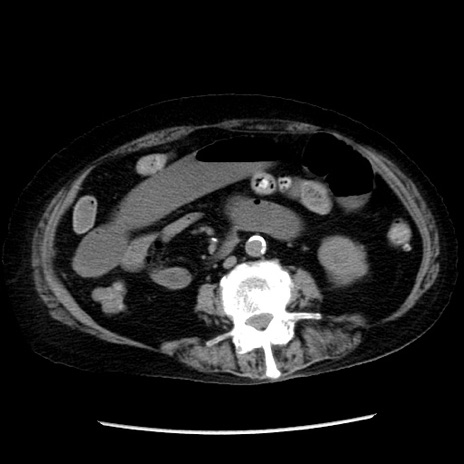

症例14(横断像)

【症例】 90歳代女性

【主訴】 腹痛・嘔吐

【現病歴】今朝から左側腹部痛を認めた。 経過観察していたが、嘔吐を認めたため来院。

【既往歴】 子宮癌術後

【身体所見】 意識清明、BP 127/54mmHg、P 98bpm Sp02 95%(RA)、BT 35.8°C、腹部平坦・軟腸ぜん動音聴取良好、右下腹部圧痛(+) 反跳痛なし

【データ】WBC 9800、CRP 0.46